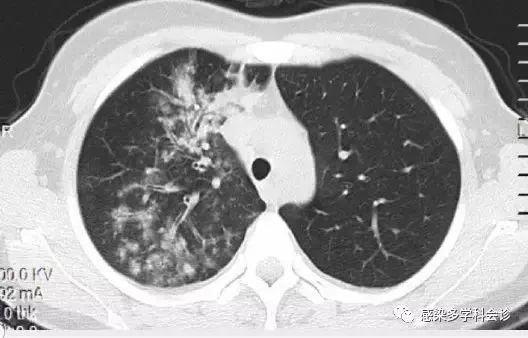

支原体肺炎:树芽征+磨玻璃影+大片实变+树雾征(晕征)+支气管壁增厚